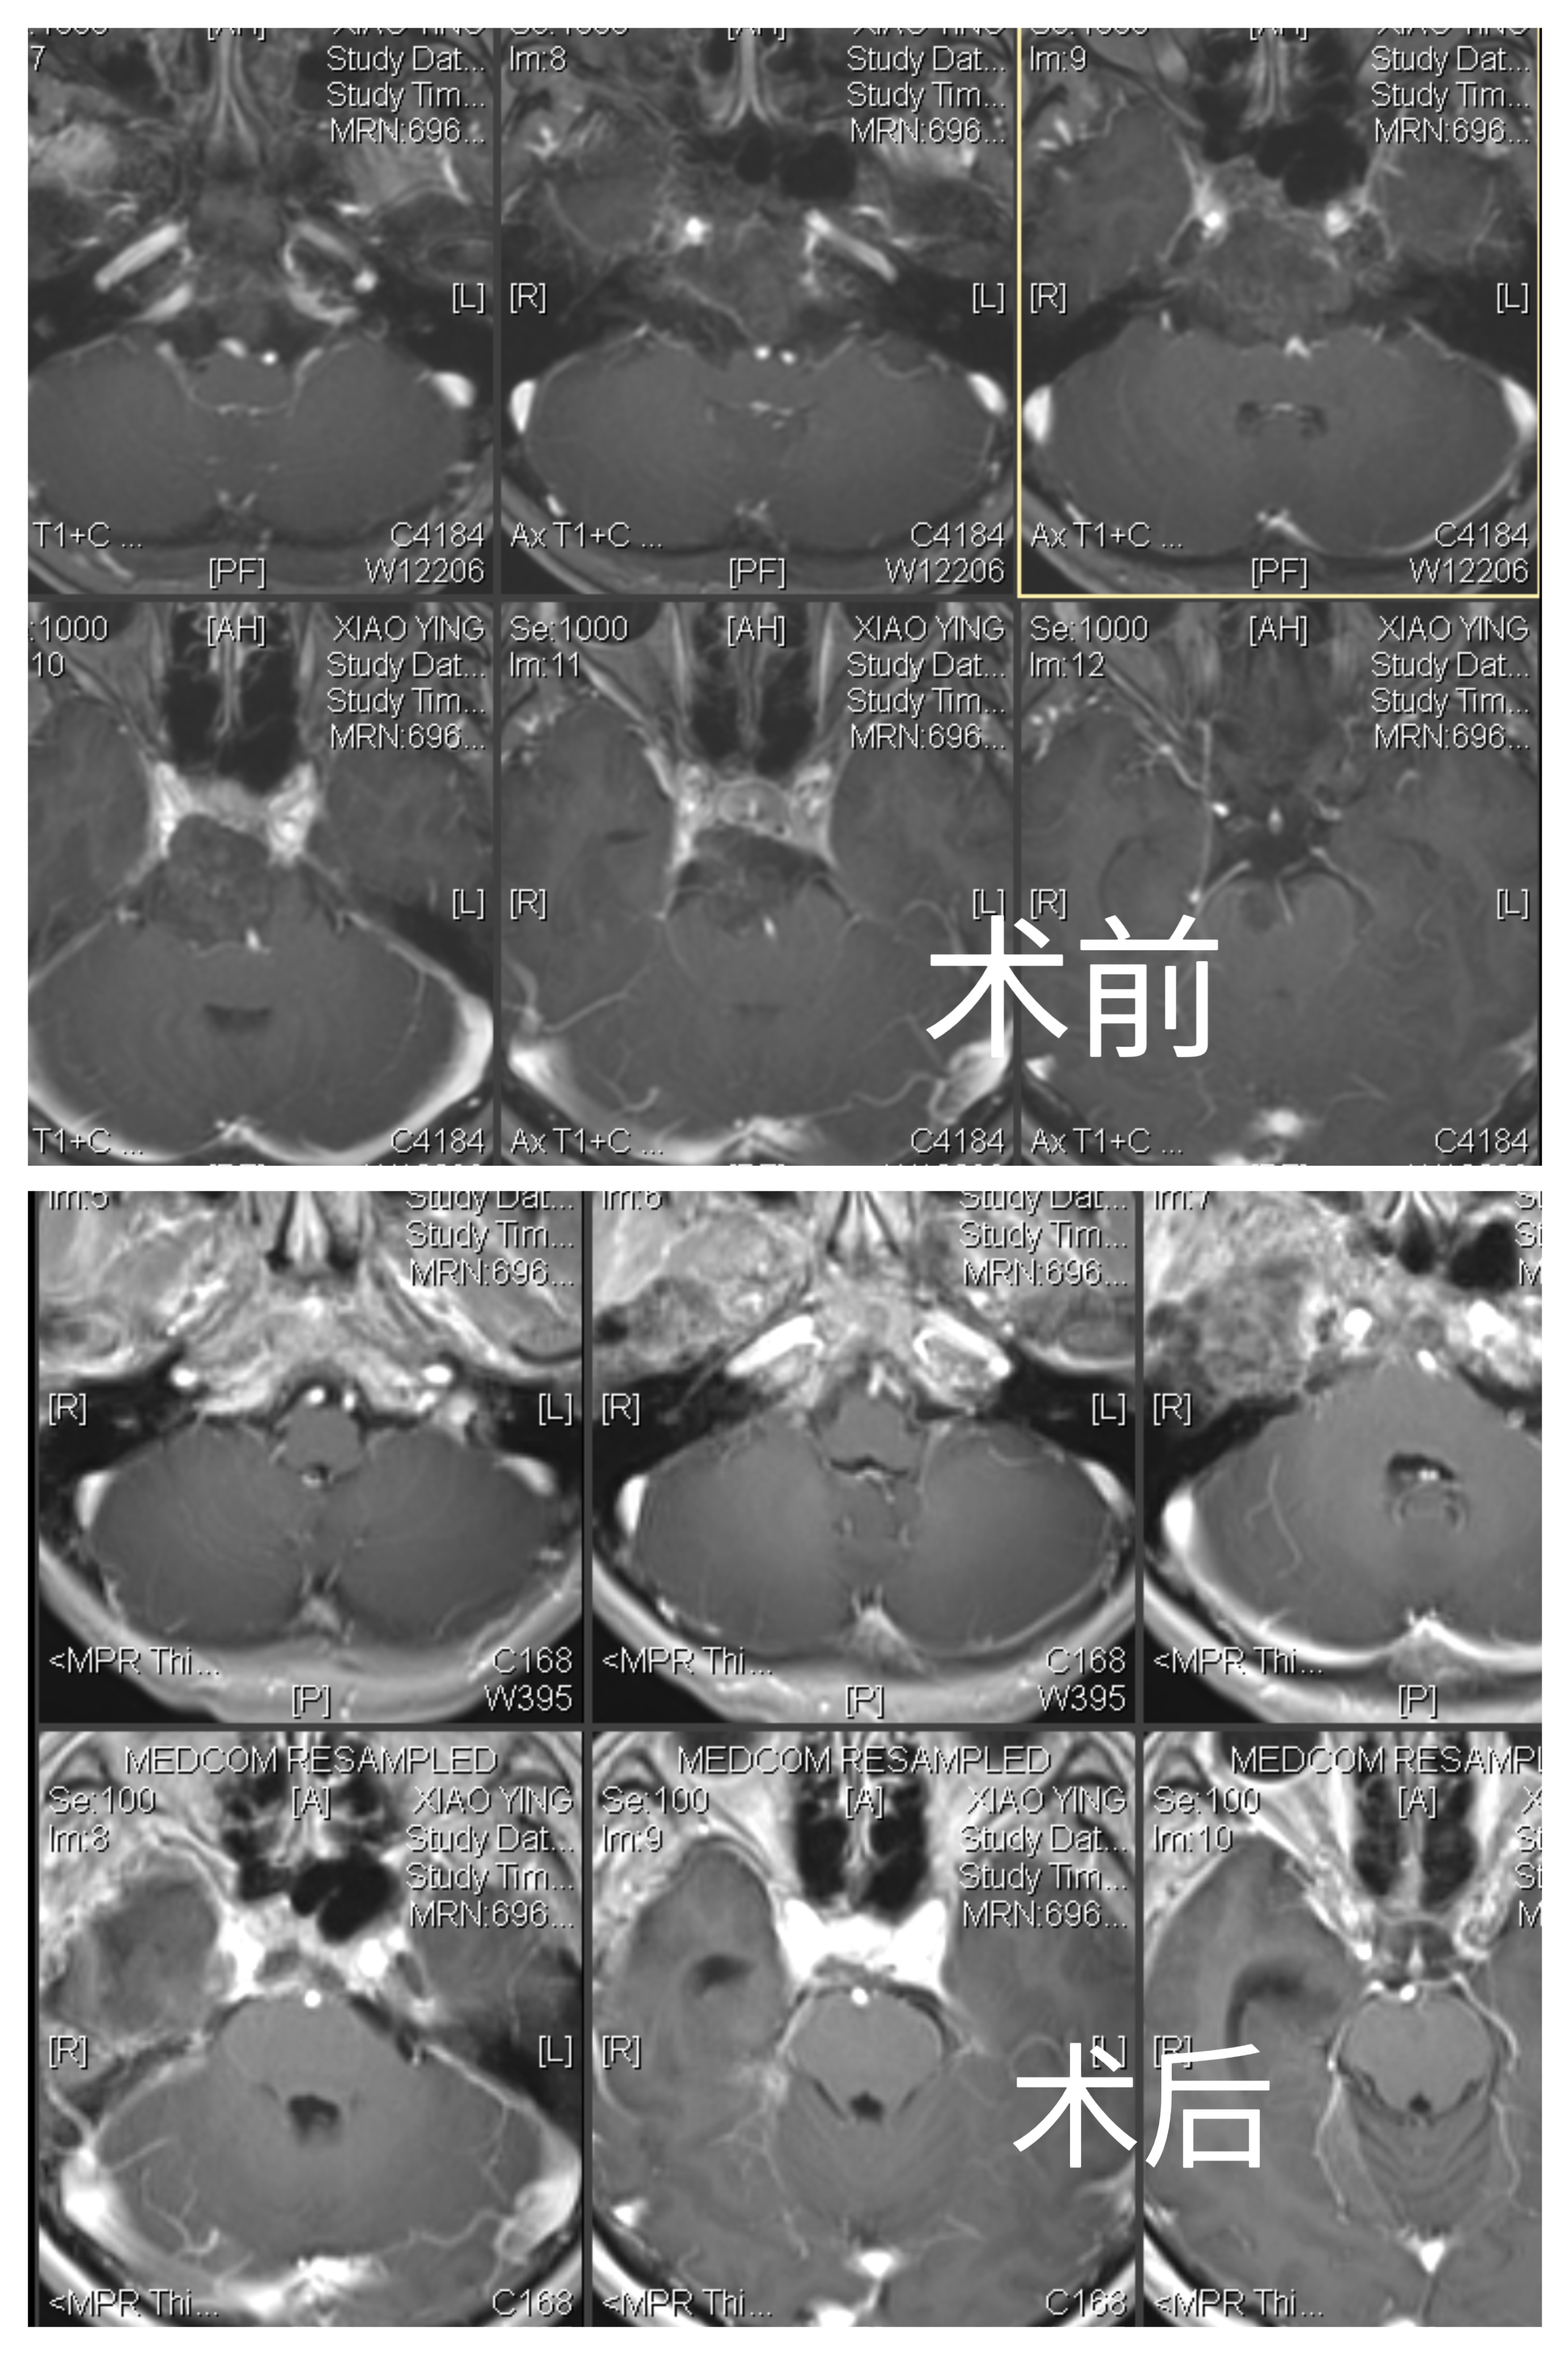

女性患者,56岁,因“视物重影4月”于2023-07-11入院。

入院诊断:斜坡脊索瘤

魔钻磨除Kawase三角,见部分肿瘤位于硬膜外,肿瘤灰黑色,质软,血供丰富,使用环形刮匙和取瘤镊分块切除肿瘤,肿瘤包膜与颅底神经黏连严重,予以部分切除。弧形剪开颞部硬脑膜,脑组织博动正常。抬起颞叶,于滑车神后方切开小脑幕,电灼岩上窦,即见肿瘤,肿瘤灰红色,质软,血供一般,与双侧IV、V、VI、I、V颅神经及基底动脉粘连。显微镜下次全切除,部分肿瘤外包膜与上述神经血管黏连严重予以保留。创面电凝和速即纱压迫彻底止血。清点器械物品无误,硬膜下置引流管1 根,使用人工硬膜缝合硬脑膜,可吸收硬膜封合胶予以加固,复位并固定骨瓣,头皮和颞肌止血后,逐层缝合颞肌、帽状腱膜和头皮。